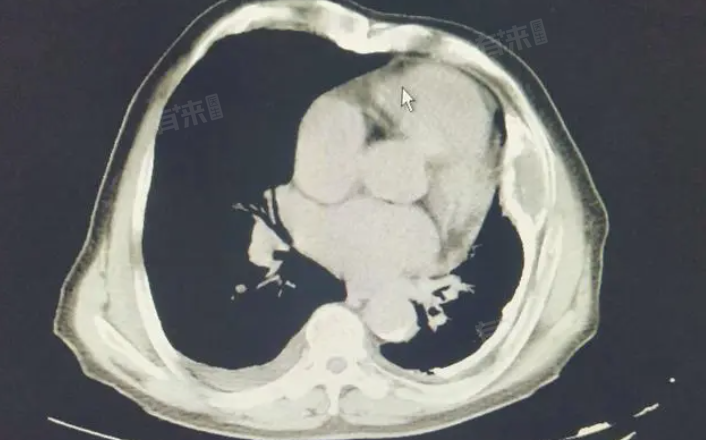

胸膜增厚伴钙化是指胸膜组织在炎症或其他病理因素作用下,出现纤维化和钙盐沉积的现象,导致胸膜厚度增加并伴随钙化灶的形成。

对于胸膜增厚伴钙化的诊断,除了依赖影像学检查外,还需要结合患者的病史、临床表现以及实验室检查等多方面信息进行综合判断。一旦确诊,应根据具体病因制定相应的治疗方案。对于由结核感染引起的胸膜增厚伴钙化,需要进行抗结核治疗;而对于由肺炎等炎症性疾病引起的病变,则需要进行抗感染治疗。